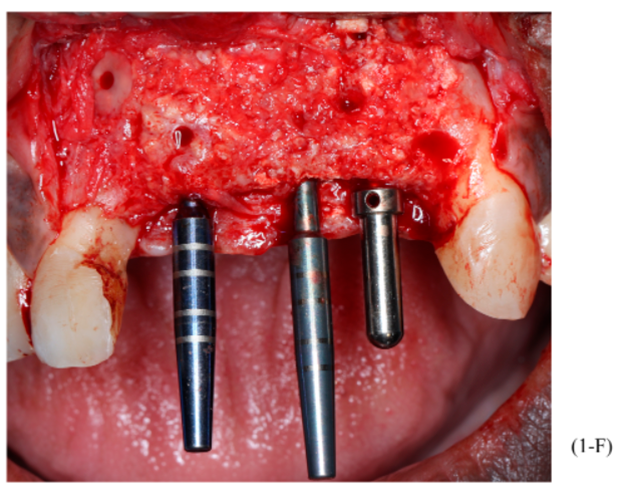

Figuras 3,4,5,6,7 e 8 – Sequência do primeiro ato cirúrgico, onde podemos observar (imagem 3) a incisão do tipo Newmann modificada para ampla visualização do campo operatório e as extrações dentárias. Podemos observar também a descorticalização do processo alveolar e a instalação dos parafusos tipo tenda Implacil De Bortoli de 10 mm, respeitando a distância de pelo menos 2 mm entre cabeças (imagem 4). Foram colocados dois gramas de biomaterial Bio-Oss Geistlich, preenchendo toda cavidade e alvéolos até a delimitação da cabeça dos parafusos (imagens 5 e 6). Antes do fechamento completo da ferida cirúrgica, colocamos membranas de PRF para auxílio na reparação tecidual e proteção do material de enxerto (imagem 7). Para fechamento da ferida cirúrgica, usamos fio do tipo Cytoplast, fornecido pela Implacil De Bortoli. É de extrema importância sua utilização, pois apresenta excelente elasticidade, acompanhando edema cirúrgico pós-operatório, o que diminui o risco de deiscência no pós-operatório.

Foram planejados três implantes do tipo Cone Morse Maestro Implacil De Bortoli 3.5 x 13 mm. Após remoção de maneira facilitada dos parafusos tenda, foram instalados três implantes em ótimo posicionamento tridimensional (imagens 1-E, 1-F, 1-G, 1-H). Todos apresentaram estabilidade primária de 35 Ncm de torque e aguardamos quatro meses para posterior reabilitação protética definitiva com próteses individualizadas de metalocerâmica do tipo parafusada.